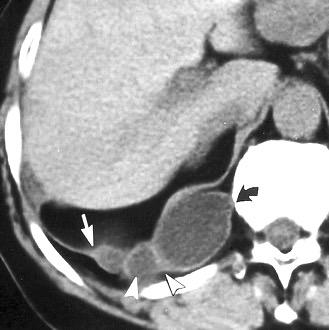

Diafragma “colgante” (“dangling sign”)

(“Dangling sign”)

TC. Mejor con multicorte. (reconstrucciones).

Asociación: Aire en pared.

Fracturas costal .Rotura esplénica. Neumoperitoneo.

Diafragma discontinúo Herniación de la grasa omental

Desser TS et al.The dangling diaphragm sign: sensitivity and comparison with existing CT signs of blunt traumatic diaphragmatic rupture. Emerg Radiol 2010